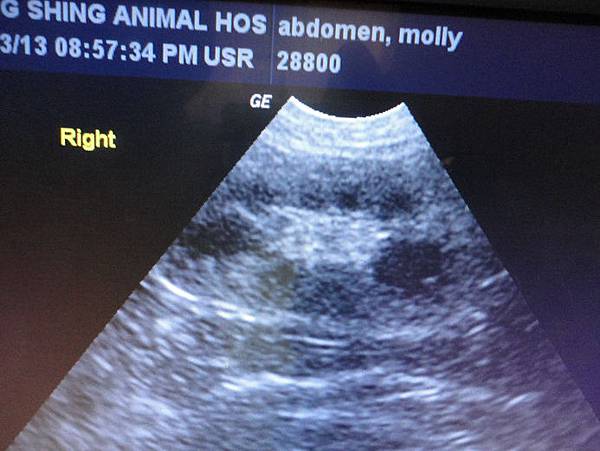

再看了腎臟

大致上還正常,但有老化的跡象